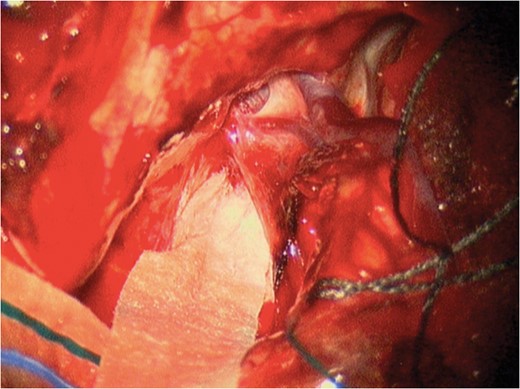

During attempted passage of the AMTS, we encountered resistance in the region of the temporal pole. In standard fashion, we had aimed the strip along the superior temporal gyrus and used brisk irrigation to separate the cortex from the dura. After two attempts, the strip was abandoned in fear of injuring vascular structures that we could not directly visualize. Subsequently, at resection, a large bridging vein complex was visualized where the strip met resistance. Intraoperative photograph demonstrating this complex is shown in Fig. 3. Our intracranial EEG study is shown in Figs 4 and 5.

Intraoperative image during part 2 (resection) demonstrating the two large temporopolar bridging veins where resistance was met while attempting AMTS passage.

Complications due to vascular injury are fortunately a rare occurrence in epilepsy surgery [4]. Tanriverdi noted four post-operative subdural hematomas in 2449 epilepsy operations (0.2%) [5]. However, the opportunity for injury to bridging veins is present, specifically during passage of subdural strips without direct visualization in a paramedian fashion [6]. Passing subdural strip electrodes are a key component of epileptogenic foci localization. It allows monitoring of difficult to access cortical areas as well as minimizing the overall surgical exposure necessary for adequate coverage. Tactile sensation guides the surgeon during passage of electrodes and signs of resistance should raise concern. This report and operative photograph should raise awareness of the location and size of bridging veins the surgeon may encounter in the temporopolar region during subdural strip passage.